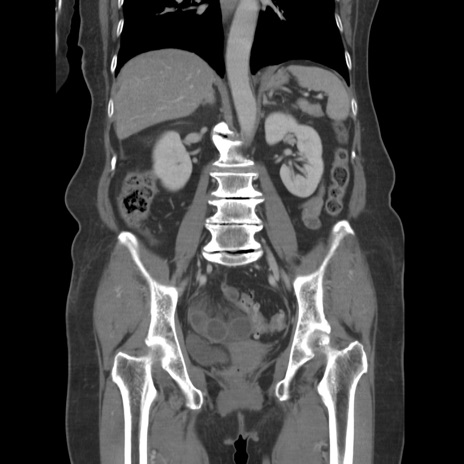

症例19(冠状断像)

【症例】80歳代女性

【主訴】下腹部痛

【現病歴】約8時間前より下腹部痛の出現あり、救急外来受診。

【既往歴】両側付属器切除

【身体所見】意識清明、下腹部正中に手術痕あり、その部位に一致して圧痛と反跳痛あり。腸蠕動音は亢進。

【データ】WBC 9300、CRP 0.15

横断像